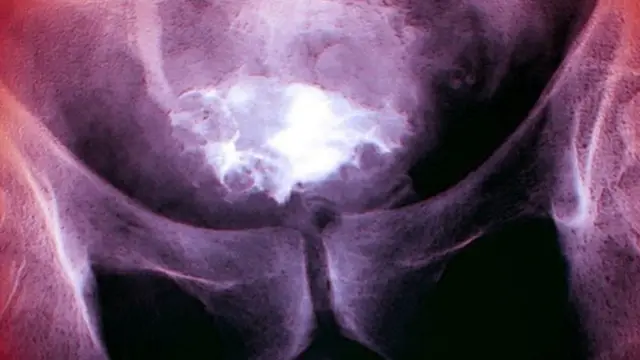

صدر الصورة، Science Photo Library